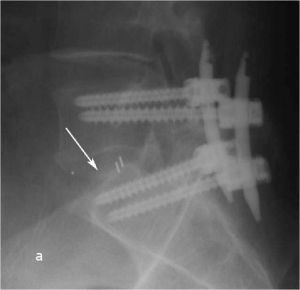

Рис. 9 a,b. Ренгенограмма поясничного отдела позвоночника в боковой (a) и прямой (b) проекции. Транспедикулярная фиксация L5-S1 позвонков титановой конструкцией канюлированными винтами, межтеловая фиксация позвонков кейджем из PEEK-керамики. Стрелкой указано положение ренген–негативного кейджа, видны титановые метки кейджа.

Рис. 10 a. Ренгенограмма поясничного отдела позвоночника в боковой (a) и прямой (b) проекции. Транспедикулярная фиксация L5-S1 позвонков титановой конструкцией канюлированными винтами, межтеловая фиксация позвонков кейджем из PEEK-керамики. Стрелкой указано положение ренген–негативного кейджа, видны титановые метки кейджа. Рис. 10 b. Ренгенограмма поясничного отдела позвоночника в боковой (a) и прямой (b) проекции. Транспедикулярная фиксация L5-S1 позвонков титановой конструкцией канюлированными винтами, межтеловая фиксация позвонков кейджем из PEEK-керамики. Стрелкой указано положение ренген–негативного кейджа, видны титановые метки кейджа.

При контрольной рентгенограмме отмечено правильное положение транспедикулярной системы и кейджа на уровне L5-S1 позвонков. (Рис.9)